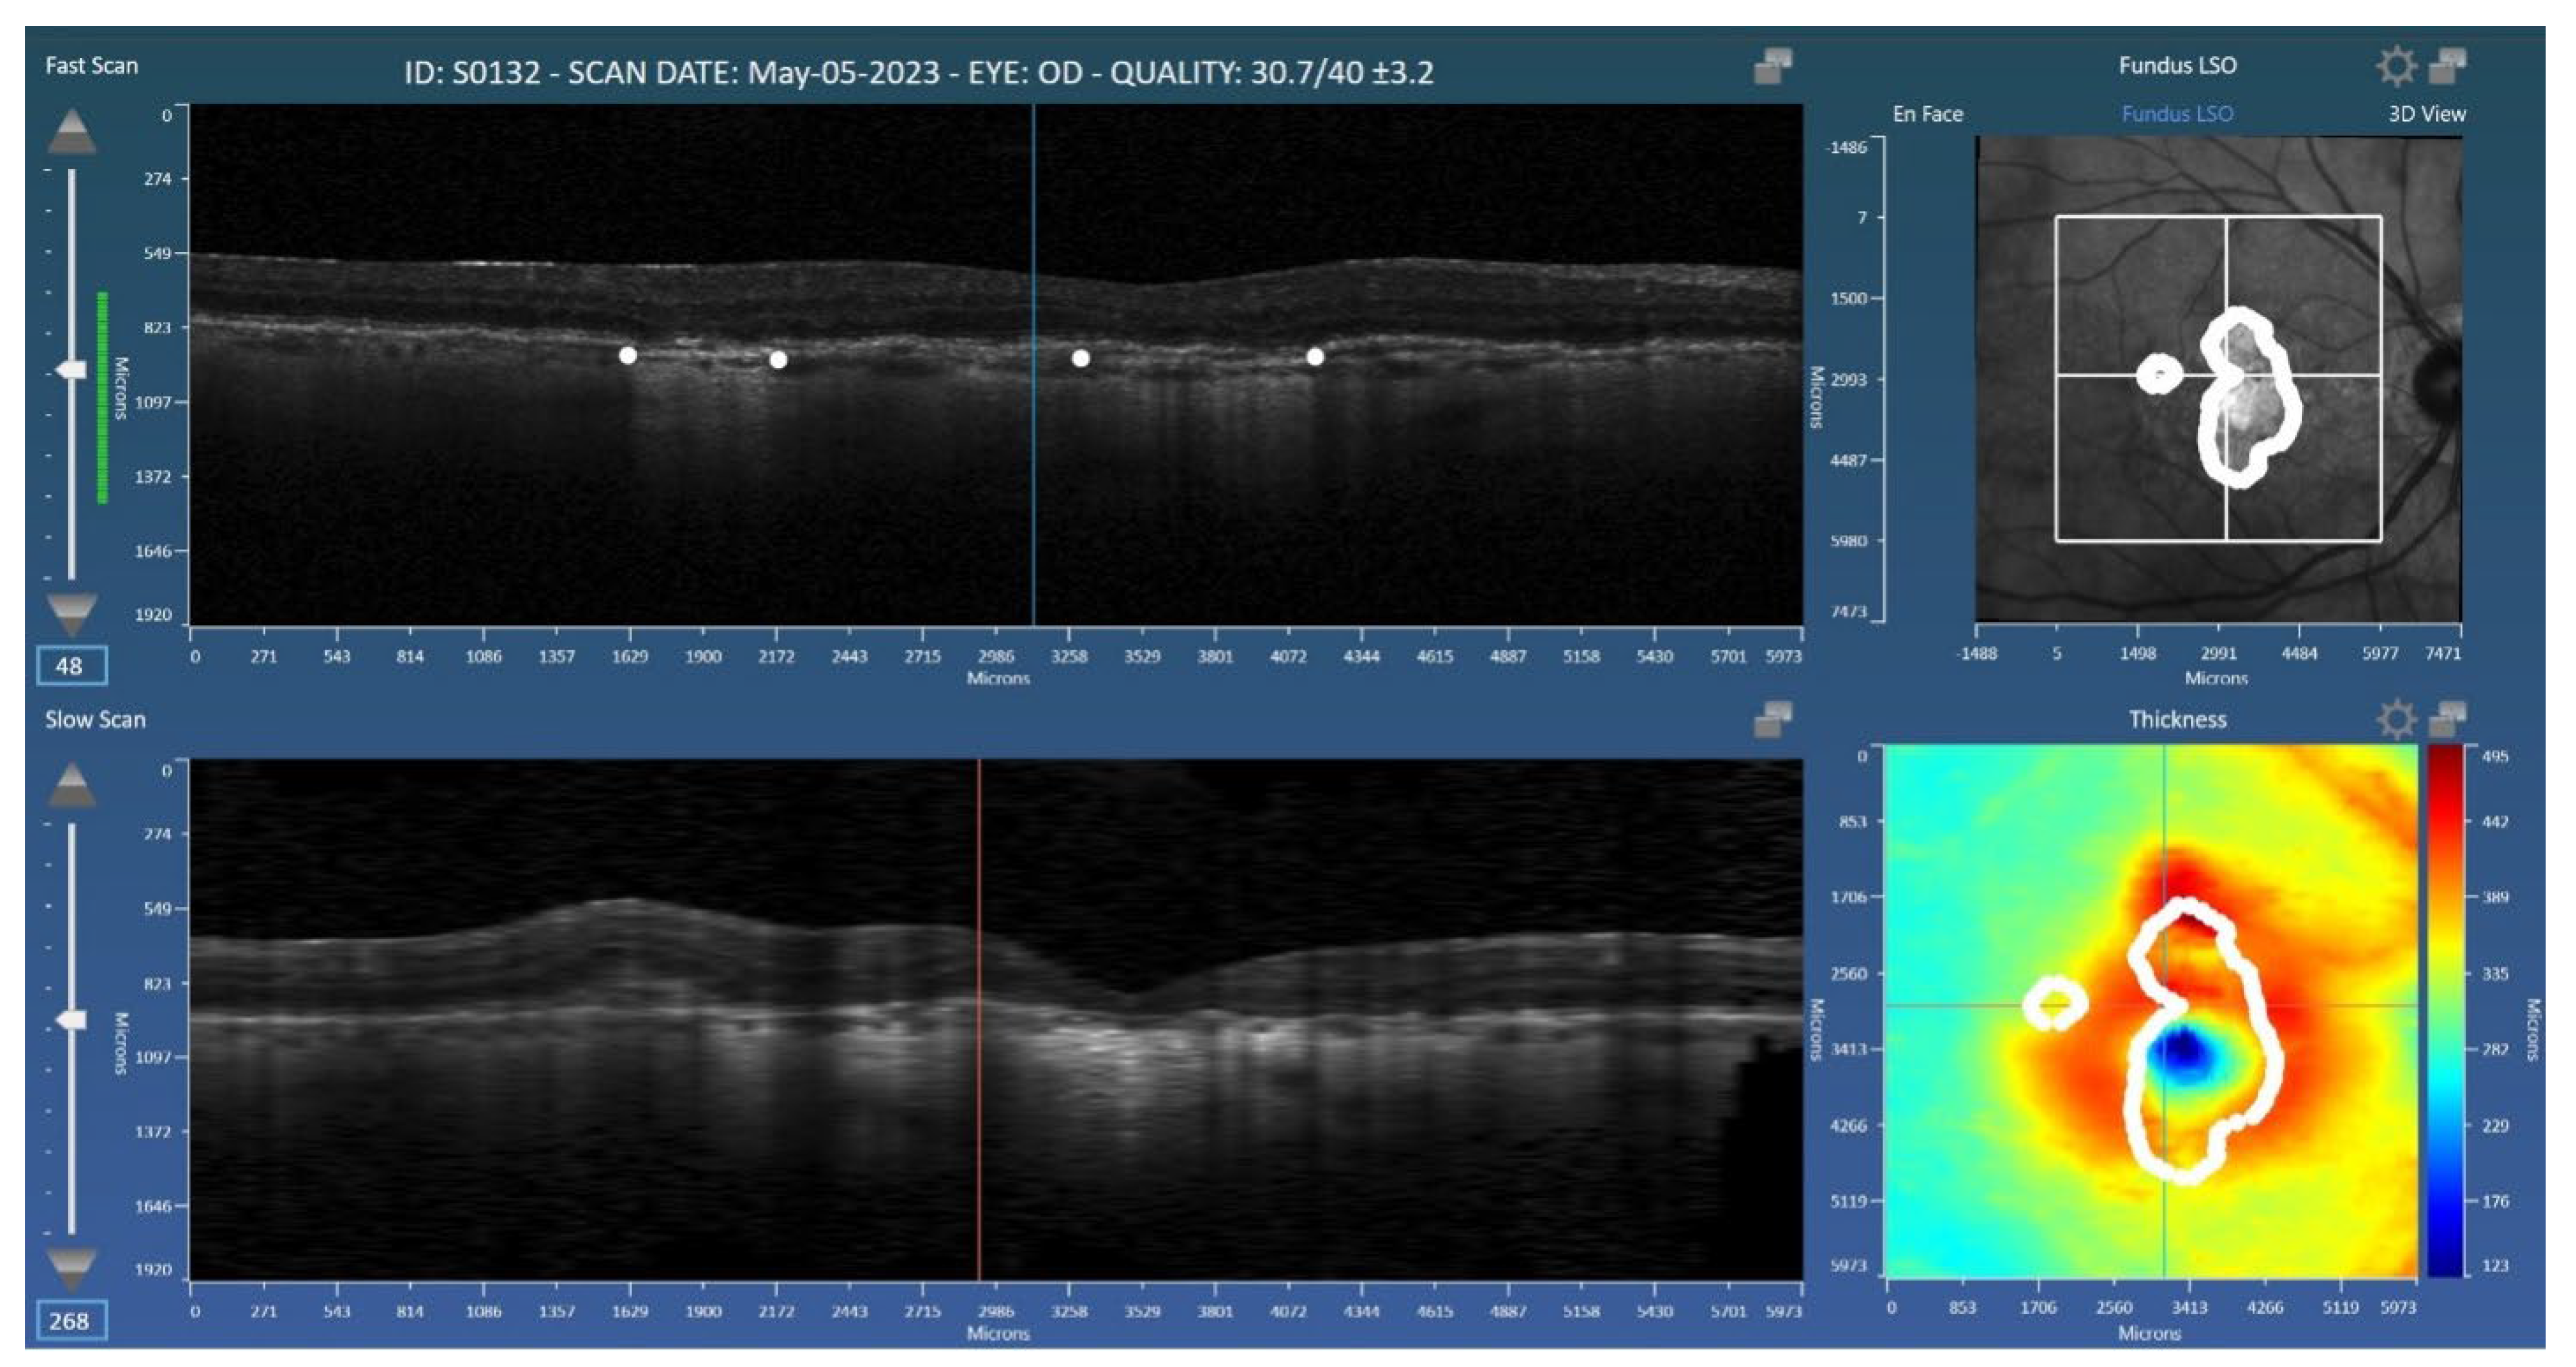

2.1. Data Collection and Grading

2.2. Grading

2.3. Deep Learning Architecture

2.4. Analysis Methods